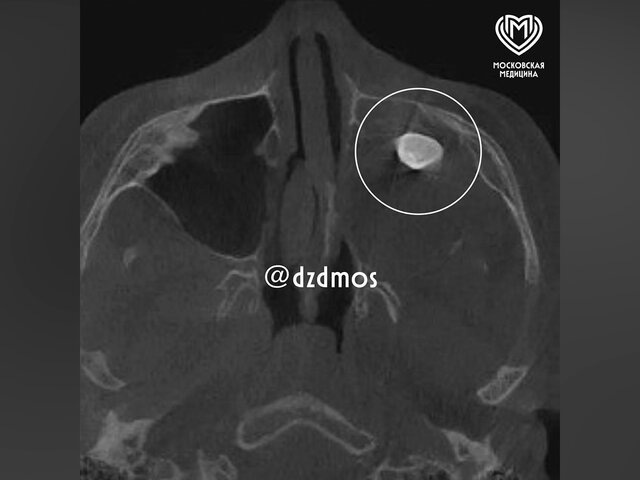

Врачи Филатовской больницы в Москве вытащили зуб из носа 15-летнего мальчика. Об этом сообщила пресс-служба департамента здравоохранения столицы. Юный пациент поступил в медучреждение с жалобами на асимметрию лица и заложенность носа. По словам хирурга-оториноларинголога Вугара Достиева, ранее мальчику уже проводили осмотр в частной клинике, в ходе которого обнаружили в гайморовой пазухе сформированный зуб. Подростку предложили провести удаление через полость носа, но родители решили проконсультироваться также и в Филатовской больнице. Там врачи провели углубленное обследование и собрали консилиум. Медики заподозрили, что ситуация вызвана нарушением формирования зубной ткани. "Мальчику нужно было провести операцию по Колдуэлу Люку, то есть обеспечить доступ через верхнюю десну, чтобы вернуть ему возможность нормально дышать. Сделав разрез, врачи обнаружили новообразование, внутри которого и находился зуб", – рассказали в медучреждении. Исследование показало, что у подростка была терато

Фото: телеграм-канал "Московская медицина"

Юный пациент поступил в медучреждение с жалобами на асимметрию лица и заложенность носа. По словам хирурга-оториноларинголога Вугара Достиева, ранее мальчику уже проводили осмотр в частной клинике, в ходе которого обнаружили в гайморовой пазухе сформированный зуб.

Исследование показало, что у подростка была тератома – эмбрионально-клеточное опухолевое образование, которое может содержать ткани различных органов. Как отметил Достиев, такие новообразования очень редко располагаются в зоне лица. В случае подростка тератома занимала практически всю левую полость носа, из-за чего ее не смогли показать ни КТ, ни рентген.